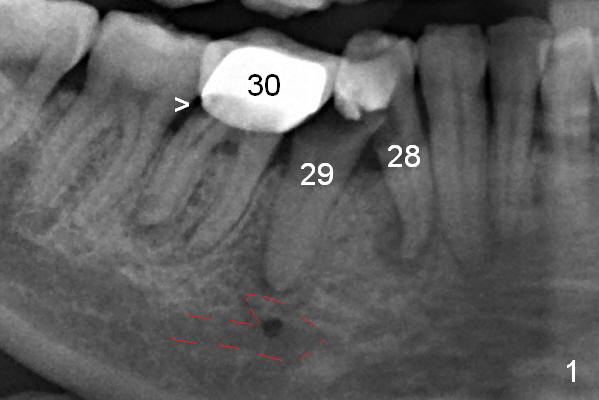

The patient returns for implant placement 11 months post extraction of #28 and 29. With flapless manner, initial osteotomy happens to drop into the original socket of #28 (Fig.4). After use of 3.3 mm Magic Drill (MD) and Final Drill for 15 mm, a 4x11 mm dummy implant is placed (Fig.5). It appears that the implant is long for the site (red dashed line: Mental Loop). However, a definitive implant (4x9 mm, IBS) has difficulty to reach its depth (Fig.6). After several rounds of untorque and retorque, the implant does not seat completely (Fig.7, implant driver disengagement) with autogenous bone placed distal (>). Retrospectively, a larger MD should have been used (3.8 mm) for complete seating in the dense bone. In fact she is post breast cancer treatment with 50% chance of relapse. The patient returns for follow up 1.5 months postop (Fig.8). The wound has healed. Impression is taken 5 months postop (Fig.9). When the crown is cemented, food impaction is an issue between the implant crown and crown at #30. Since the tooth #30 is mesially tilted with distal open margin and apical infection, the tooth will be extracted. Osteotomy is going to be initiated in the mesial slope of the mesial socket (Fig.9 red line). An implant will be placed more or less in the mesial socket (green box).